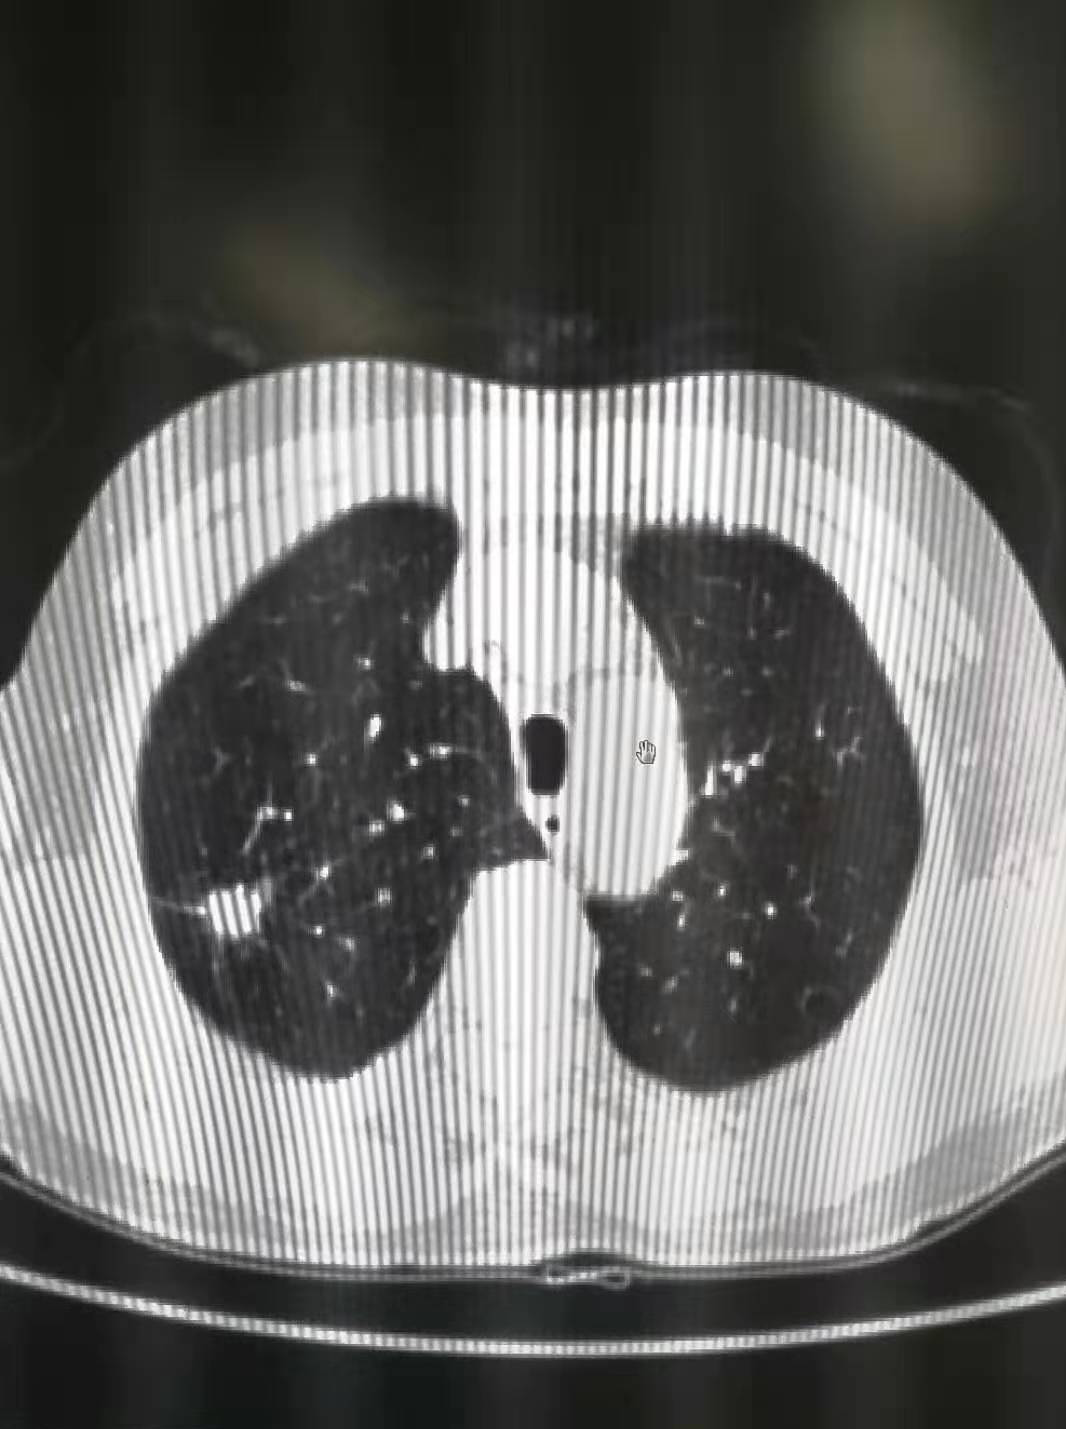

患者郭某某,女, 67歲,以“間斷咳嗽、咳痰、氣短6年,胸背部疼痛1月"為主訴入院。輔助

檢查:胸部CT平掃:右肺上葉結(jié)節(jié),性質(zhì)待定,兩肺肺氣腫、肺大泡。進(jìn)一步完善PET-T檢查,提示:

1.右肺上葉高密度實(shí)性結(jié)節(jié)影,核素異常高代謝,考慮,肺癌。遂聯(lián)系胸外科行手術(shù)根治治療,術(shù)后

病理回報(bào): (右肺上葉)中分化腺癌,未侵及胸膜。(第七組)淋巴結(jié)未查見癌轉(zhuǎn)移(0/2) 。該患者已

通過手術(shù)達(dá)到根治。